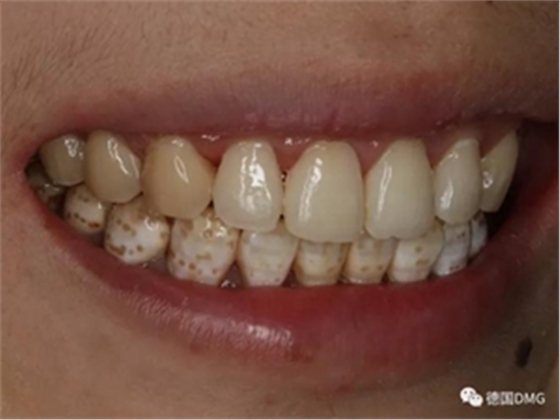

(下圖是拋光完成)

治療完成的上頜牙齒和未治療的下頜牙齒形成明顯對比。

治療前和治療后的對比,患者很高興很滿意。